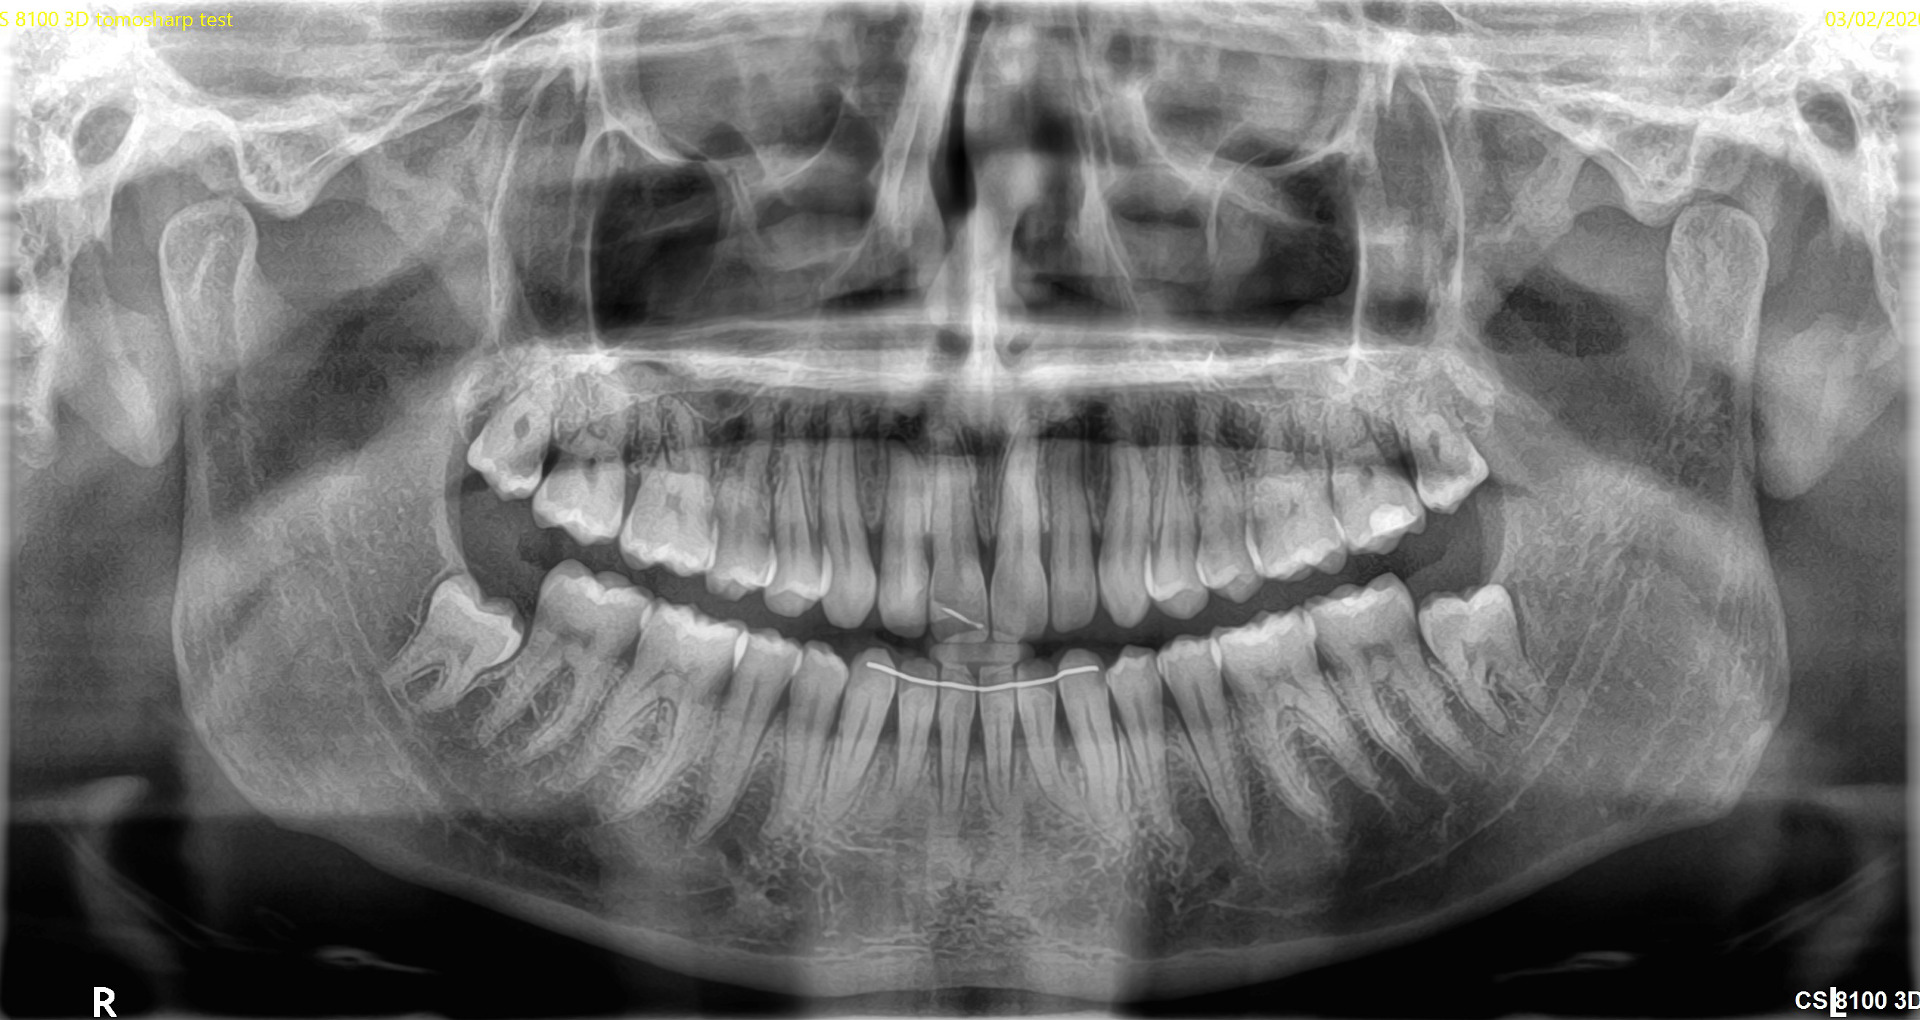

- 3D skenēšana un radiogrāfija nodrošina detalizētus attēlus par zobiem, žokļiem un apkārtējiem audiem.

- Datortomogrāfija (CT) sniedz trīsdimensiju attēlus, kas nepieciešami sarežģītām procedūrām, piemēram, implantācijai vai sakņu kanālu ārstēšanai.

Mūsu speciālisti izmanto progresīvas tehnoloģijas – trīsdimensiju skenēšanu, rentgenu, intraorālās kameras un datortomogrāfiju, lai precīzi identificētu visas mutes dobuma problēmas.